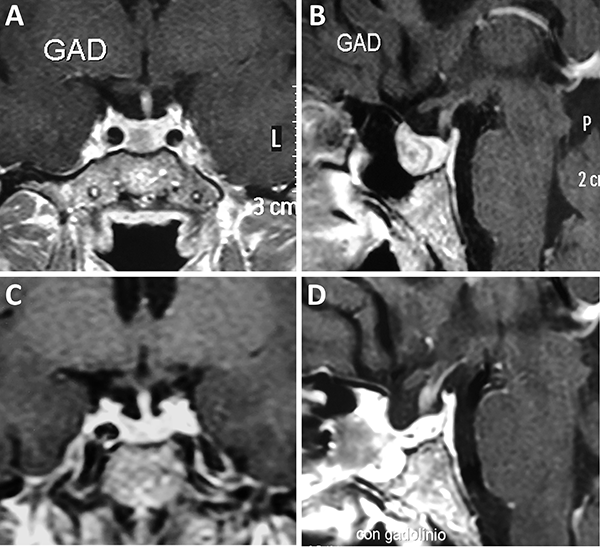

Una clasificación clásica de los adenomas es según su tamaño. Se los clasifica en microadenoma <10 mm (fig. 2), macroadenoma >10 mm (fig. 3), y adenoma gigante > 30 mm (fig. 4). Esta clasificación es importante ya que los índices de remisión están ligados al tamaño del adenoma y también su recidiva.12

Figura 2: Microadenoma. A-B: RM preoperatoria; C-D: RM postoperatoria.